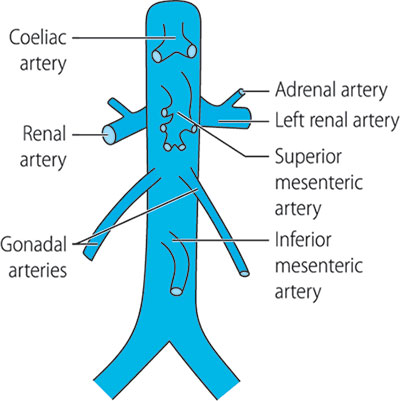

Abdominal vasculature

The abdominal aorta starts at the diaphragmatic opening at the level of the T12 vertebral. It usually descends slightly to the left of the vertebral column and terminates at the level of L4 where it divides into the two common iliac arteries (Figure 1.13). The major visceral branches of the aorta are the coeliac axis, superior and inferior mesenteric arteries, suprarenal arteries, renal arteries and spermatic arteries. Parietal branches (parietal = relating to the walls of a part or cavity) are the phrenic, lumbar and sacral arteries.